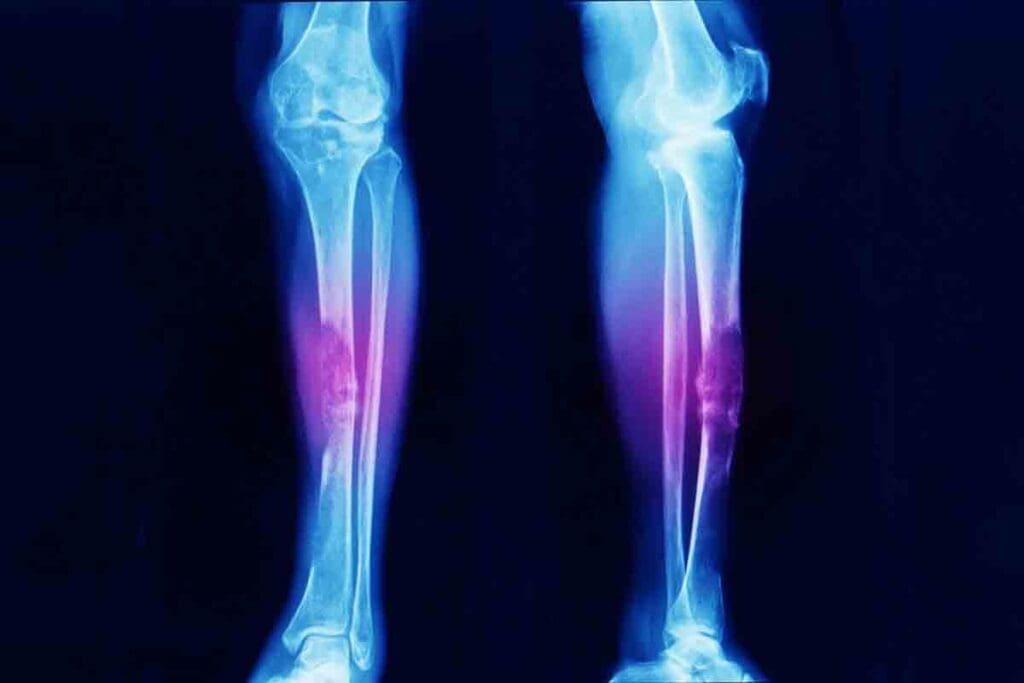

Ewing sarcoma is a serious and aggressive cancer. It usually starts in the bones or soft tissues of young people. It grows fast and can spread, so quick diagnosis and treatment are key.

It’s more common in Caucasians but can happen in anyone. The tumor often appears in long bones, the pelvis, or the chest wall.

The symptoms of Ewing sarcoma depend on where and how big the tumor is. Common signs include pain and swelling, and sometimes fever and weight loss. People often think it’s just a sports injury at first.

There might also be a noticeable lump, more so if the tumor is in a soft tissue. If it’s in the spine or pelvis, it can cause nerve problems or make it hard to move. It’s important to be careful and not delay diagnosis in young patients with ongoing pain.

Anatomical Location and Its Impact on Prognosis

Ewing sarcoma can happen in the body’s bones. The axial skeleton, like the skull and spine, has a worse outlook than the appendicular skeleton, which includes the limbs.

Tumors in the limbs (appendicular skeleton) usually have a better chance of recovery. But, tumors in the pelvis or chest (axial skeleton) are harder to treat because of their closeness to important parts and the complexity of surgery.